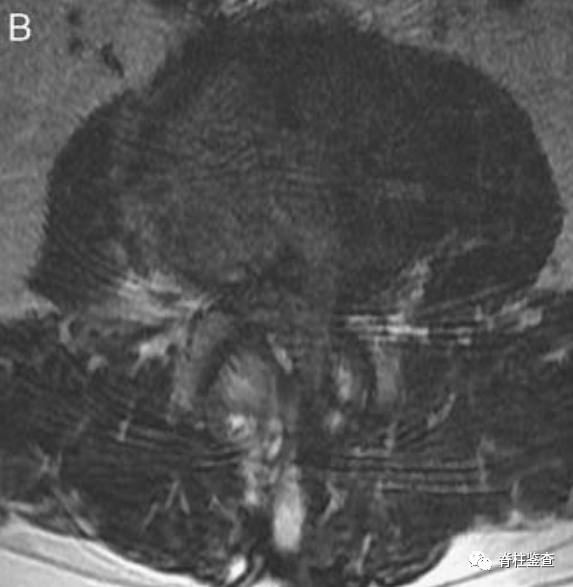

术后第1天显示,椎间盘充分移除;MR图像中的瘢痕组织限制了硬膜囊的充分扩张(白色↓)。